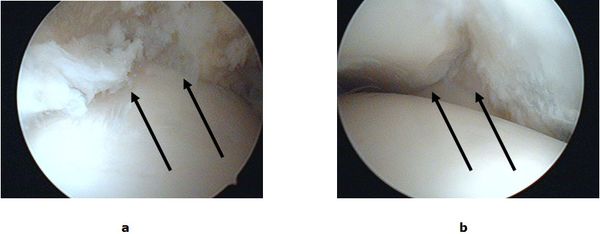

Abb.2: a Eingeklemmtes Narbengewebe im Gelenkspalt. b Freie Einsicht in den Gelenkspalt nach Entfernung des Narbengewebes.